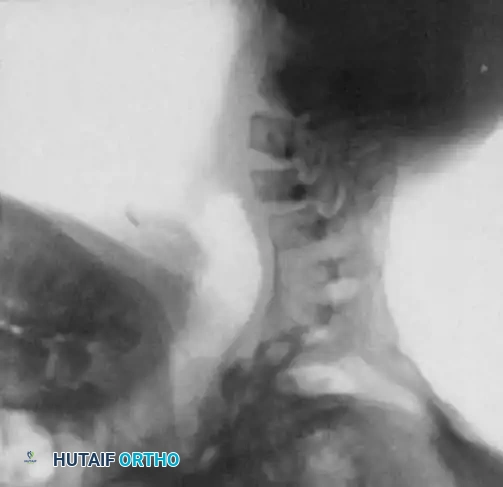

Fig. 38-219 A, Preoperative lateral radiograph of a pediatric patient with achondroplasia demonstrating severe, rigid thoracolumbar kyphosis.

Fig. 38-219 B & C, Postoperative anteroposterior and lateral radiographs demonstrating successful spinal arthrodesis with pedicle screw instrumentation, restoring sagittal balance without neurological compromise.

Additional imaging demonstrating the complex osseous anatomy and pedicle morphology that must be navigated during instrumentation in skeletal dysplasias.